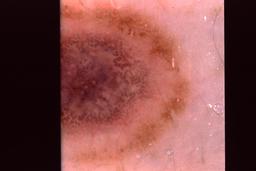

{

"age_approx": 55,

"anatom_site_general": "anterior torso",

"concomitant_biopsy": true,

"dermoscopic_type": "contact non-polarized",

"diagnosis_1": "Benign",

"diagnosis_2": "Benign melanocytic proliferations",

"diagnosis_3": "Nevus",

"diagnosis_4": "Blue nevus",

"diagnosis_confirm_type": "histopathology",

"image_type": "dermoscopic",

"lesion_id": "IL_0179653",

"melanocytic": true,

"patient_id": "IP_3482172",

"sex": "male"

}